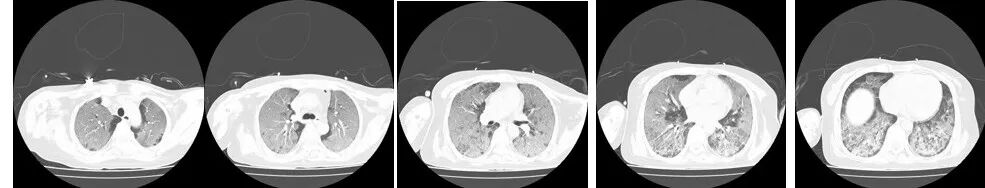

图4(2024年10月8日 D22)胸部CT示双肺弥漫性渗出性改变较前吸收,双下肺渗出较前明显吸收。

图5(2024年10月15日 D29)胸部CT示双肺弥漫性渗出性改变较前明显吸收,仅双上肺可见。